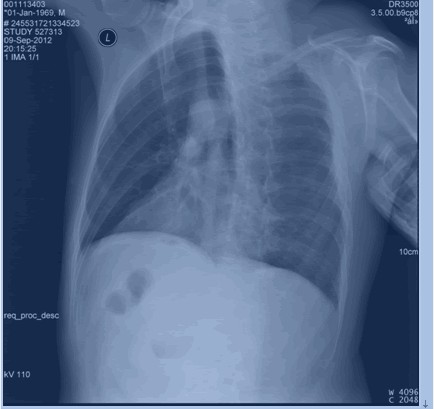

后肋骨折

图示为右侧3,5,6,7,8后肋骨折。

(2)斜位